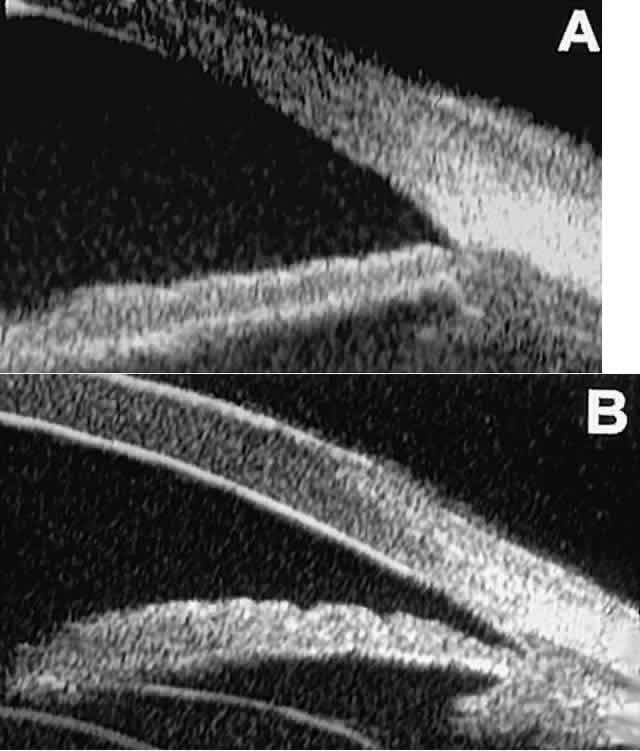

Fig. 14. UBM features of eyes with Peter's anomaly. A. Mild posterior central corneal excavation, absence of Descemet's membrane and endothelium centrally, iridocorneal adhesions to margins of corneal defect, and diffuse hyper-reflectivity of corneal stroma. B. Different patient showing detail of posterior central corneal excavation and diffuse hyper-reflectivity of corneal stroma.

Fig. 15. UBM features of miscellaneous corneal disorders. A. Corneal edema appears as thickening of superficial layer of cornea; corneal stroma is thinner than normal and abnormally bright. B. Bullous keratopathy appears as localized separation of corneal epithelium from Bowman's membrane filled with clear serous fluid. C. Band keratopathy appears as dense, brightly reflective subepithelial plaque in peripheral cornea. D. Postinflammatory corneal scarring after keratitis; note nonuniform corneal thickness and abnormal reflectivity of corneal stroma.